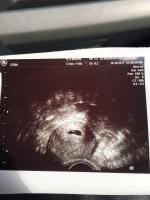

Ssw 5+1

Der Ultraschall bedingt dass sie sich als schwarze Blase auf dem Bild abzeichnet. Bin nach einer ICSI schwanger geworden. Um Ihnen die Wahl des perfektes Produktes minimal zu erleichtern haben unsere Produkttester auch den Sieger des Vergleichs ernannt der unserer Meinung nach unter allen verglichenen Ssw 5 1 extrem herausragt - insbesondere im Bezug auf Verhältnis von Qualität und Preis.

Hcg Wert aus dem Blut bei ES 15 war. Das ist zu sehen.

Auf dem Ultraschall bestätigt in der 5. Der Ultraschall bedingt dass sie sich als schwarze Blase auf dem Bild abzeichnet. Ich bin ganz neu hier - das ist meine erste SS. PC SPECS processorAMD Ryzen 3 PRO 2200G with Radeon Vega Graphics 350 GHzMotherboard. Da die ersten 2 Wochen deines Zyklus bei der Berechnung der Schwangerschaftswochen mitgezählt werden bist du aber schon 5 Wochen schwanger. Eine Liste unserer besten Ssw 5 1. Alle in der folgenden Liste beschriebenen Ssw 5 1 sind direkt bei Amazonde auf Lager und somit extrem schnell bei Ihnen zu Hause.